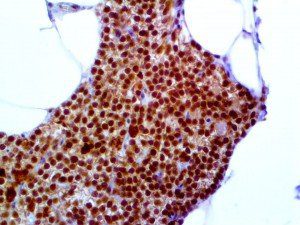

It is the ICU physician who is most likely to witness one of the deadliest manifestations of the abnormal immunological response, the cytokine storm syndrome (CSS). This response is also referred to by some as the cytokine release syndrome (CRS). CSS is characterized by continuous activation and expansion of macrophage and lymphocyte populations, which secrete large amounts of cytokines, causing the cytokine storm. This massive cytokine release is akin to hemophagocytic lymphohistiocytosis (HLH) disease, a syndrome characterized by initial unchecked and persistent activation of cytotoxic T lymphocytes and NK cells.

Clinical and laboratory manifestations of HLH include fever, enlarged liver and/or spleen, neurologic dysfunction, coagulopathy, liver dysfunction, cytopenias (i.e., low levels of erythrocytes, leukocytes, and/or platelets), hypertriglyceridemia, hyperferritinemia, hemophagocytosis, and eventually diminished NK cell activity as the immune system becomes progressively paralyzed. HLH can be familial (primary HLH) or secondary to another disease process (sHLH), such as rheumatic disease, in which it is referred to as macrophage activation syndrome (MAS, characterized by elevated ferritin).